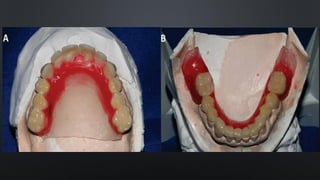

FORMATO DOS ARCOS

FORMA DOS ARCOS

• VARIÁVEL ENTRE OS INDIVÍDUOS

• ALTERÁVEL POR FATORES

EXTERNOS (EX: RESPIRADOR

BUCAL)

• PARABÓLICA: SEGMENTO ANTERIOR CURVADO COM LEVE DIVERGÊNCIA DOS

SEGMENTOS POSTERIORES

• TRIANGULAR (EM V): ESTREITA NO SEGMENTO ANTERIOR E COM

DIVERGÊNCIA NOS SEGMENTOS POSTERIORES

• OVÓIDE: RELATIVA CURVATURA DO SEGMENTO ANTERIOR COM LEVE

CONVERGÊNCIA DOS SEGMENTOS POSTERIORES

• QUADRADA (EM U): SEGMENTO ANTERIOR PRATICAMENTE RETO E

SEGMENTOS POSTERIORES PARALELOS

• RELACIONADA COMO CRESCIMENTO ÓSSEO E DESENVOLVIMENTO DENTÁRIO FORMA DOS ARCOS • VARIÁVEL ENTRE OS INDIVÍDUOS • ALTERÁVEL POR FATORES EXTERNOS (EX: RESPIRADOR BUCAL)

• PARABÓLICA: SEGMENTOANTERIOR CURVADO COM LEVE DIVERGÊNCIA DOS SEGMENTOS POSTERIORES FORMA DOS ARCOS

• TRIANGULAR (EMV): ESTREITA NO SEGMENTO ANTERIOR E COM DIVERGÊNCIA NOS SEGMENTOS POSTERIORES FORMA DOS ARCOS

• OVÓIDE: RELATIVACURVATURA DO SEGMENTO ANTERIOR COM LEVE CONVERGÊNCIA DOS SEGMENTOS POSTERIORES FORMA DOS ARCOS

• QUADRADA (EMU): SEGMENTO ANTERIOR PRATICAMENTE RETO E SEGMENTOS POSTERIORES PARALELOS FORMA DOS ARCOS